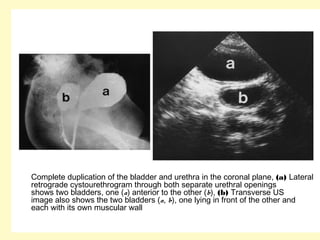

Complete duplication of the bladder and urethra in the coronal plane, (a) Lateral

retrograde cystourethrogram through both separate urethral openings

shows two bladders, one (a) anterior to the other (b), (b) Transverse US

image also shows the two bladders (a, b), one lying in front of the other and

each with its own muscular wall